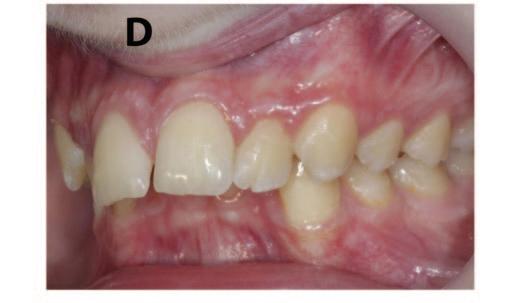

After lunch, orthodontist Dr Shane Higgins spoke on orthodontic problems and solutions in managing the mixed dentition. Using a range of clinical examples, he outlined the treatment planning and decision-making process around proposed extractions of first permanent molars of poor prognosis, impacted incisors, and double teeth. He gave tips on how to measure crowding, and discussed the importance of a timely orthodontic consultation to plan for future treatment. He concluded by saying that issues in the mixed dentition can be complex, and timing is crucial, but there are guidelines available to assist clinicians, and he advised seeking specialist advice if you’re not sure how to proceed.